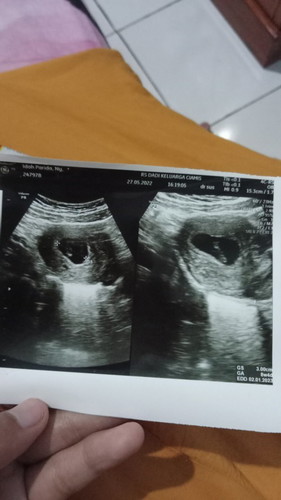

Flek coklat di usia kehamilan 9w3d

Hallo bund,mau sdikit cerita. Pas hari minggu kmrn sya ada flek sedikit cuma setitik kecil,udah itu gaada lg. Selang sehari ada lagi dan sama cuma setitik kecil.dan hari ini ada flek lagi cuma agak banyakan bukan lagi setitik. Kira kira aman gk ya bund? Btw Bulan desember kmrn saya ngalamin hamil BO dan harus d kuret.dan itu jga yg bikin worry dikehamilan sekarang kadang sering waswas gitu apalagi skrg lg ngflek gini pikirannya udah kmana mana. Sblmnya saya blm usg krna kata bidannya nunggu usia kehamilannya 3bulan aja biar udah keliatan janinnya. Tadinya sya mau usg hari ini krna cemas,cuma baru ngeuh kalo skrg dr nya gaada jadwal usg. Sarannya dong bun yg pernah ngalamin flek juga d usia hamil muda. #bantusharing #seriusnanya